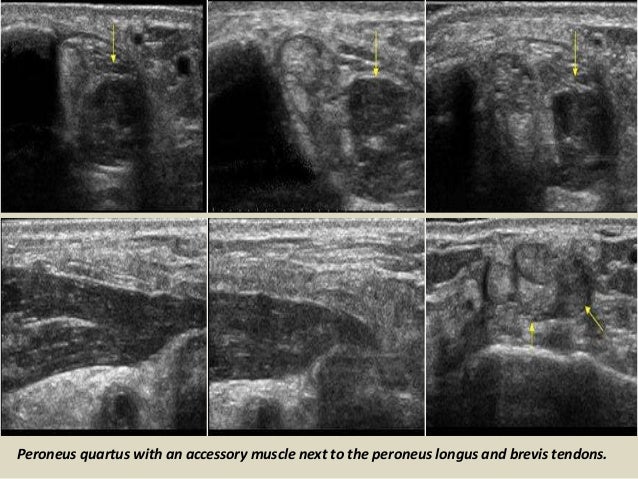

Peroneus quartus with an accessory muscle next to the peroneus longus and brevis tendons.

49. 49. Peroneus quartus with an accessory muscle next to the peroneus longus and brevis tendons.